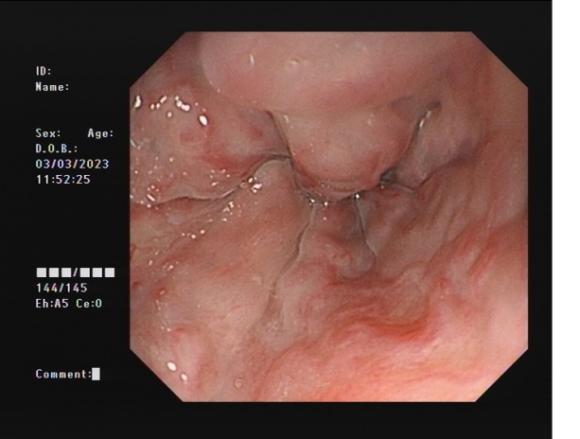

直腸側向發育性腫瘤 內鏡下黏膜下剝離術后創面

內鏡下黏膜剝離術(ESD):治療巨大平坦息肉,早期癌及癌前病變,黏膜下腫瘤等。